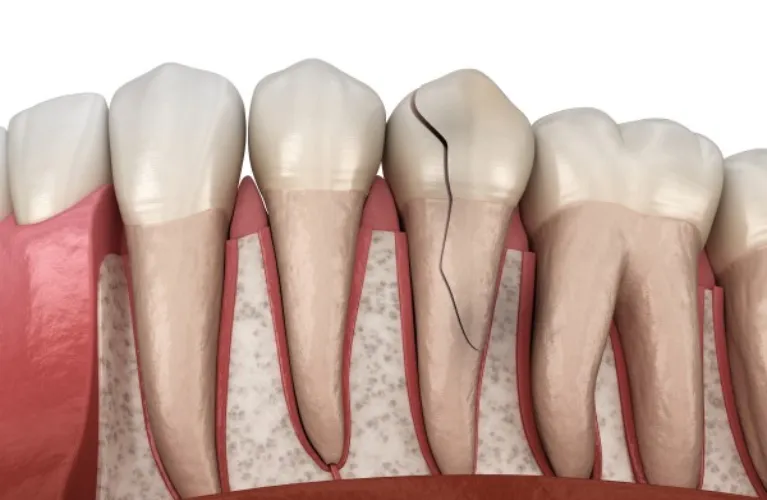

Fractured or broken teeth:

If a tooth is severely fractured or broken, extraction may be the best solution.